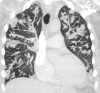

This case study is a rare example of cardiac hydatidosis in a high-income country, where a middle-aged man presented with a ruptured right ventricular cyst causing anaphylaxis, pulmonary emboli and dissemination of Echinococcus throughout the lung. He survived the cyst rupture and underwent cardiac surgery but had incomplete resection and experienced progressive cardiopulmonary hydatidosis despite antihelminthic therapy. As a result, he experienced an array of cardiopulmonary sequelae over his lifespan. This case report highlights rare clinical manifestations of hydatid disease and potential complications of its treatment.